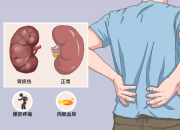

对于肾脏,大家可能是既熟悉又陌生,它是人体的重要器官,负责过滤血液中的废物、调节水分和电解质平衡、维持血压和产生红细胞等。慢性肾病(CKD)是全球重要的公共卫生问题,影响超过8.5亿人,数据表明,预计到2040年,慢性肾病将成为全球导致预期寿命缩短的第五大病因。慢性肾病早期往往没有明显症状,因此容易被忽视,当肾脏功能严重受损时,可能会导致肾衰竭,甚至需要透析或肾移植来维持生命。根据中国医师协会肾脏